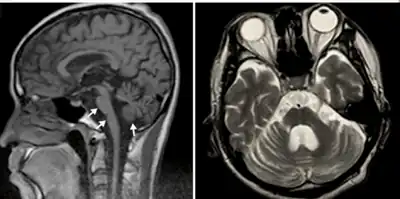

| MRI shows olivopontocerebellar atrophy. | |

Additional Parkinson-plus syndromes include Pick's disease and olivopontocerebellar atrophy.[6] The latter is characterized by ataxia and dysarthria, and may occur either as an inherited disorder or as a variant of multiple system atrophy. MSA is also characterized by autonomic failure, formerly known as Shy–Drager syndrome.[7]